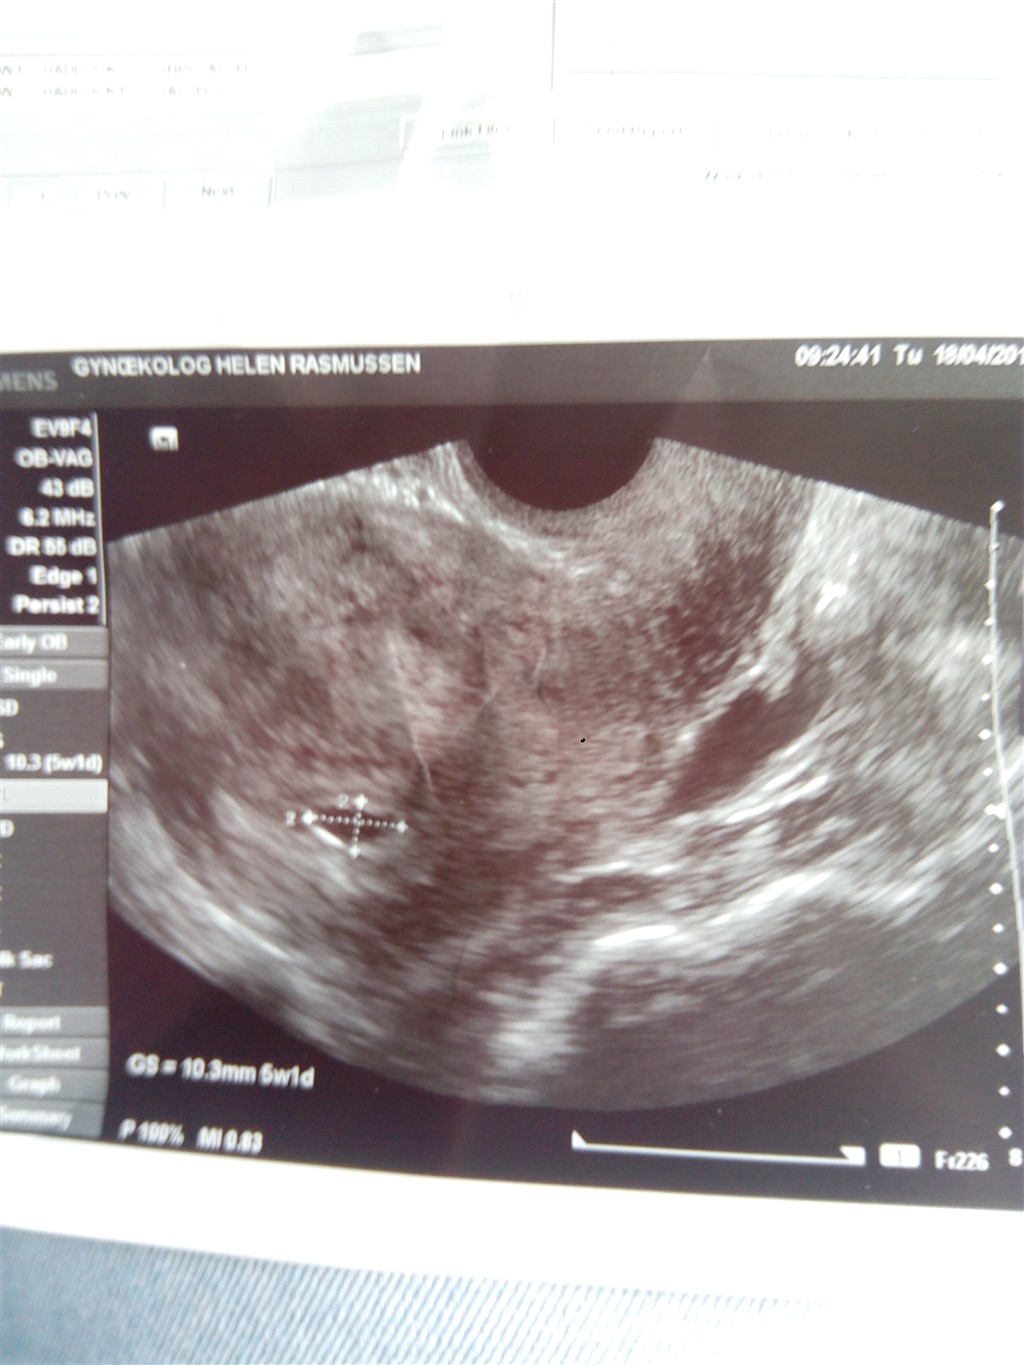

Jeg går stadig og venter på nogle symptomer på at jeg er gravid. Det eneste jeg kan mærke er at jeg er træt men hverken kvalme eller opkast (7-9-13) endnu. Så jeg har lidt svært ved at forstå at jeg faktisk er gravid. Skal gerne være i uge 5+6 så symptomerne skal nok komme men jeg er nok bare lidt utålmodig